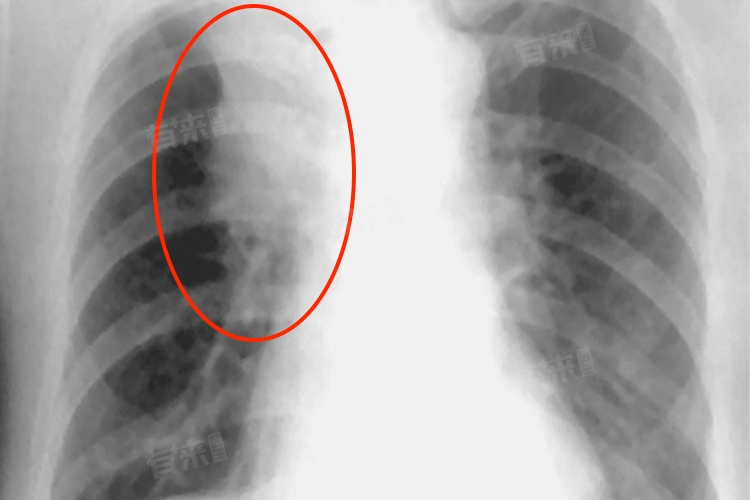

肺结节呈磨玻璃状是指在肺部影像学检查中,结节表现为密度轻度增高的云雾状淡薄影。这种表现通常是由于肺部局部组织的密度发生了改变,使得在X光、CT等影像检查中呈现出类似磨玻璃的外观。

- 另一方面,早期肺癌也可能表现为磨玻璃状肺结节。尤其是一些不典型腺瘤样增生、原位腺癌等早期肺癌病变,常常以磨玻璃结节的形式被发现。对于这种情况,医生通常会结合结节的大小、形态、边缘特征以及患者的病史、家族史等因素进行综合判断,确定是否需要进一步的检查和治疗。

- 此外,一些良性的非炎症性病变,如肺局部出血、肺淋巴管平滑肌瘤病等,也可能出现磨玻璃状肺结节。对于发现磨玻璃状肺结节的患者,医生一般会建议定期复查胸部CT,观察结节的变化情况。如果结节在随访过程中逐渐增大、密度增高、出现实性成分等变化,可能提示恶性病变的可能性增加,需要进一步进行活检或手术切除以明确诊断。